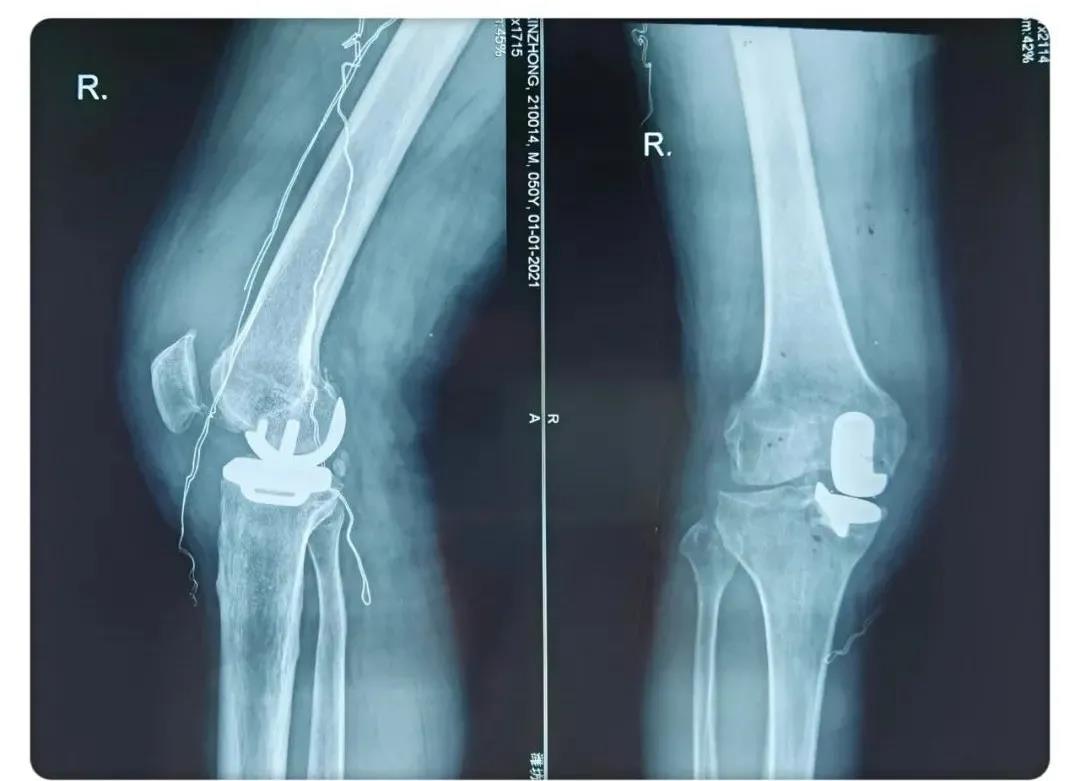

術(shù)后患者X線片

術(shù)后患者膝關(guān)節(jié)側(cè)位片

術(shù)后患者膝關(guān)節(jié)正位片